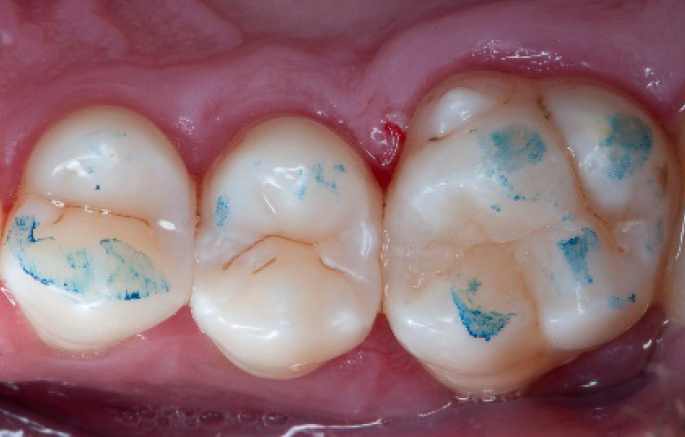

Step 2:

Initial cavity preparation, protecting the adjacent tooth with a Palodent1 WedgeGuard.

Step 3:

Class II cavity prepared.